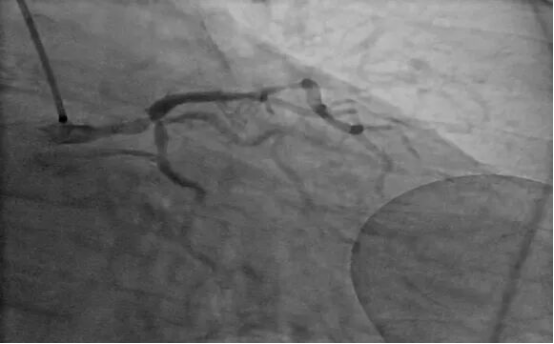

74岁的师先生(化名)怎么也没想到,近一周的胸闷气短,竟是心脏发出的严重警告,师先生的冠脉造影结果提示左主干分叉严重病变,狭窄程度85%-90%,这种情况犹如心脏供血的主干道发生严重堵塞,随时可能引发大面积心危及生命。

(术前造影图像)